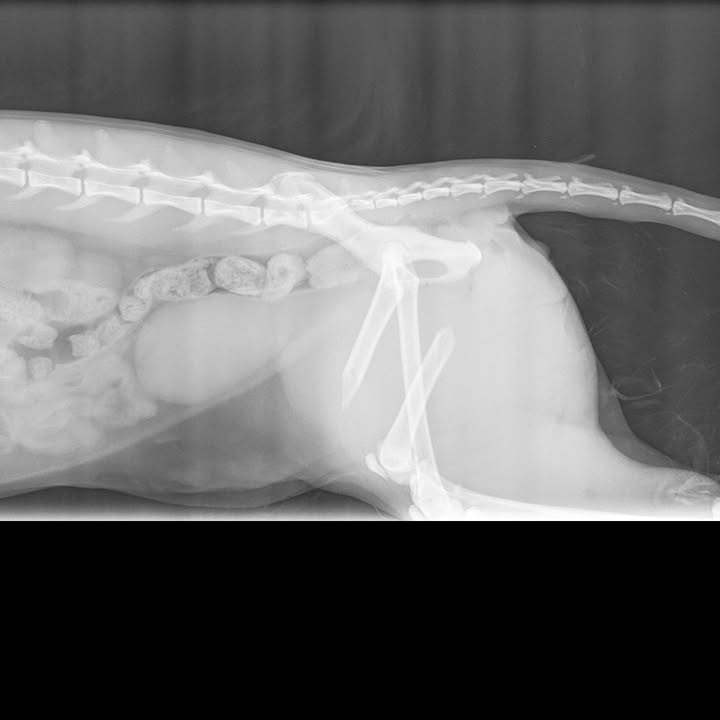

Otrzymaliśmy informację o kotku po wypadku, który został przeznaczony do eutanazji. Simba – bo tak ma na imię, żył przy domu na jednej z wsi w województwie podkarpackim. Jego opiekunka/karmicielka, znalazła go kilka dni temu leżącego i cierpiącego – ewidentnie po uderzeniu przez samochód.

Jak się okazało w lecznicy, leczenie obejmować będzie długą hospitalizację i pochłonie ogromne koszty 🙁